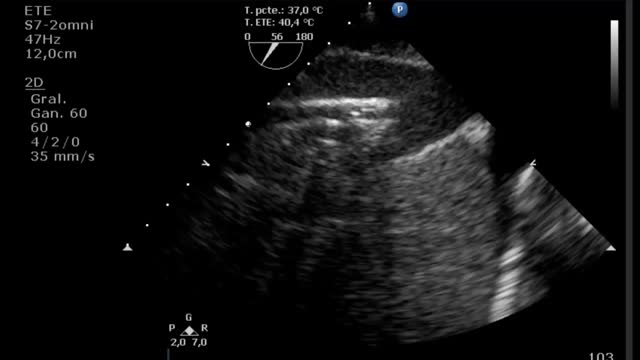

Durante la canulación, mediante la ecografía, podremos comprobar la inserción intravascular de las guías y posterior de las cánulas. En caso de uso de cánula de doble luz es indispensable la ETE, ya que puede haber complicaciones graves durante su implante (perforación de la AD o cava superior, migración al VD) y se debe comprobar una correcta orientación del flujo de retorno hacia la válvula tricuspídea21. En canulación con doble cánula simple, puede utilizarse la ETT o la ETE en ausencia de una buena ventana acústica. En la configuración fémoro-yugular, la cánula de drenaje debe quedar en la cava inferior por debajo de la vena suprahepática izquierda y el extremo de la de retorno a nivel de la AD (fig. 2) (suplementario 3). En la configuración fémoro-femoral, la cánula de drenaje debe quedar en la cava inferior y la de retorno en la AD. La distancia entre ambas cánulas debe ser al menos de 10cm para evitar la recirculación.

En la evaluación para el implante de una ECMO VV otro factor esencial es la función del ventrículo derecho (VD). Muchos pacientes con síndrome de distrés respiratorio agudo grave presentan hipertensión pulmonar y disfunción del VD en relación con la hipoxia, la hipercapnia, el aumento de la presión de las vías aéreas y la ventilación mecánica. La ECMO VV, al corregir la hipoxia y la hipercapnia, disminuye la poscarga y puede mejorar la función del VD de manera que se corrija la inestabilidad hemodinámica. En caso de presentar una disfunción ventricular derecha significativa será importante realizar un seguimiento ecocardiográfico y, si se perpetúa la situación de shock y no mejoran los parámetros ecocardiográficos a pesar de la ECMO VV, habría que plantear un cambio de estrategia a un VA o veno-arteria-vena. Para la evaluación de la disfunción del VD valoraremos: desplazamiento sistólico del plano del anillo tricuspídeo<16mm, onda S’<10cm/s, fracción de acortamiento<35%, relación área telediastólica VD/VI>0,6 significativa y >1 grave o aplanamiento/abombamiento (en forma de «D») del septo interventricular tanto en sístole como en diástole (suplementario 1). Esta interdependencia se puede cuantificar a través del índice de excentricidad ventricular, que es el cociente entre el diámetro septo-cara inferior y cara anterior-cara inferior en sístole y diástole, siendo su valor normal=118.